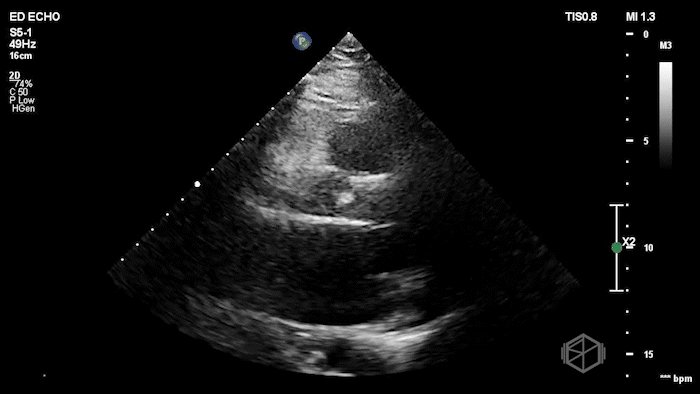

Here is the POCUS:

The POCUS shows a probably borderline LV systolic function. There is significant mitral valve calcification present. There is a mobile echodensity present near the mitral valve. On the color doppler there is severe mitral regurgitation.

In the ED, markedly elevated troponin (~42,000) and BNP 1520. Cardiology TTE revealed a 1.4 × 0.7 cm mobile echodensity on the mitral valve, concerning for papillary muscle or chordal rupture, with differential also including flail leaflet vs. vegetation, in the setting of wall motion abnormalities. The patient had a cath that showed severe triple-vessel CAD, prompting IABP placement and ICU admission. TEE confirmed severe MR due to chordal rupture with preserved LV function. She eventually did get a mitral valve replacement, but had a complex course and ultimately was made comfort care.

Diagnosis: Chordal rupture, acute severe mitral regurgitation